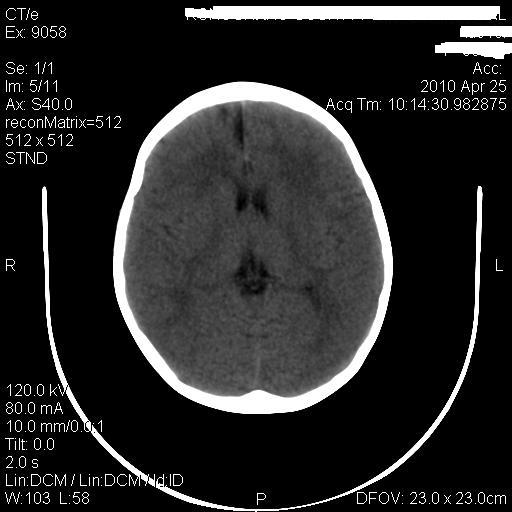

标题: PED3218:3岁女孩,曾有外伤史。未提供前片 [打印本页]

标题: PED3218:3岁女孩,曾有外伤史。未提供前片

发育略有障碍。欢迎大家发言。谢谢!

考虑右侧额顶叶脑软化灶并脑穿通畸形。

考虑:1)右侧额顶叶脑软化灶并脑穿通畸形。2)胼胝体发育不良。

右侧额顶叶脑软化灶并脑穿通畸形

支持考虑:1)右侧额顶叶脑软化灶并脑穿通畸形。2)胼胝体发育不良。

1)右侧额顶叶脑软化灶。2)胼胝体发育不良?

右侧顶叶软化灶并穿通畸形

考虑右侧额顶叶软化灶并脑穿通畸形,胼胝体发育不全。

还有脑室周围白质软化症